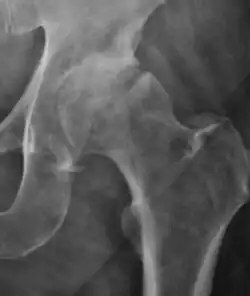

Projectional radiography ("X-ray") is the first imaging technique of choice in hip pain, not only in older people with suspected osteoarthritis but also in young people without any such suspicion. In this case plain radiography allows categorization as normal hip or dysplastic hip, or with impingement signs, pincer, cam, or a combination of both.[1]

X-Ray

Projectional radiography ("X-ray") is currently useful not only in older people in whom osteoarthritis of the hip is suspected but also in younger people without osteoarthritis, who are being evaluated for femoroacetabular impingement (FAI) or hip dysplasia.[1]

Plain radiography allows us to categorize the hip as normal or dysplastic or with impingement signs (pincer, cam, or a combination of both). Besides these, pathologic processes like osteoarthritis, inflammatory diseases, infection, or tumors can also be identified (Figure 1).[1]

Figure 1.

-

Radiography in normal hip -

X-ray in pincer impingement type of hip dysplasia -

X-ray of cam -

Hip in osteoarthritis -

Septic arthritis

![Figure 2B. Hip dysplasia.[1]](./_assets_/X-ray_of_measurements_in_hip_dysplasia.jpg)